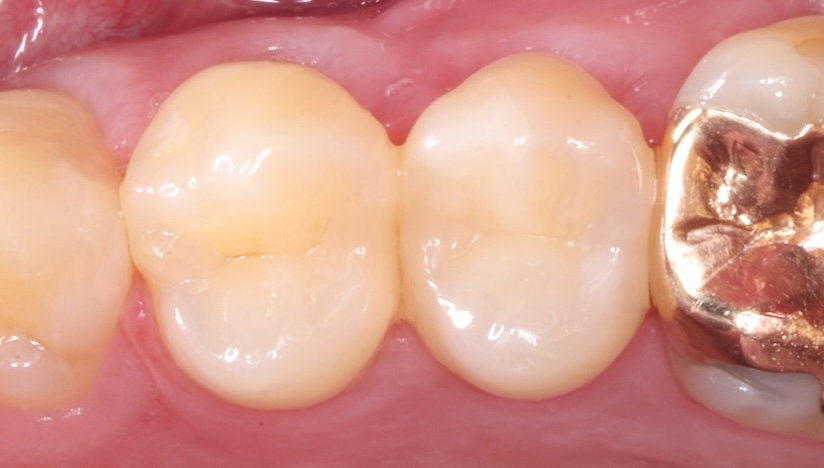

主訴

他院で抜歯してインプラントと言われた。

治療内容

リトリートメント(再根管治療・大臼歯)、ファイバーポストコア、セラミッククラウン

治療期間

3ヶ月

治療費用

374,000

治療の

リスク

根尖部透過像が完全に消失しない可能性があります。